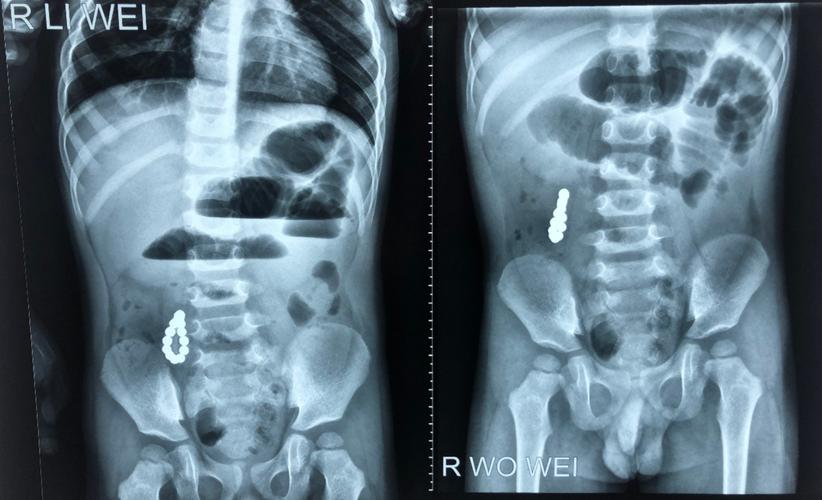

患儿的腹部平片

手把手教你阅读平片之腹部平片与消化道造影

腹部平片

腹部立位平片

腹部立位片